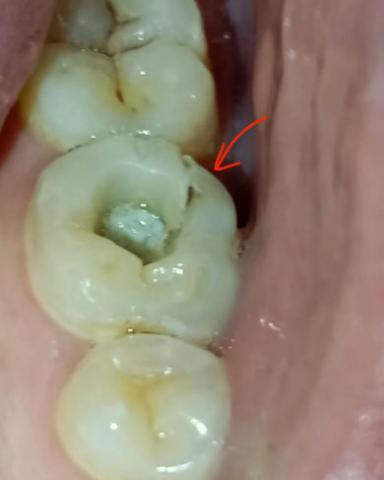

The image shows a back molar tooth with a small occlusal cavity and a visible gum-side pocket or irritation (indicated by the arrow). This suggests early tooth decay combined with localized gum involvement.

Posterior molar with small cavity on the chewing surface

Early enamel breakdown visible in the fissure

Possible plaque or early decay inside the pit

Gum tissue beside the tooth appears recessed or irritated

Narrow space between tooth and gum creating a food trap

No visible fracture of the tooth structure

Adjacent teeth appear intact